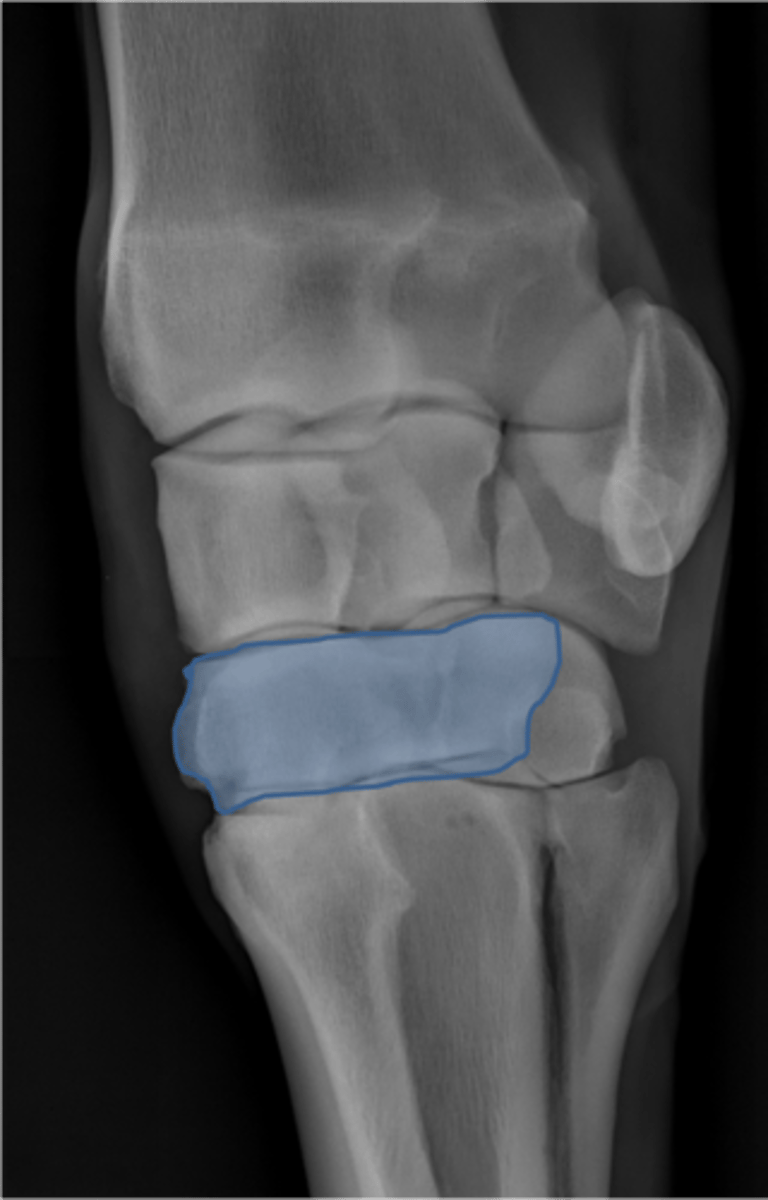

Carpus, lateral

ID joint and view

Antebrachiocarpal joint

Middle carpal joint

Carpometacarpal joint

Radial carpal bone

Intermediate carpal bone

Ulnar carpal bone

Third carpal bone

Second carpal bone

Fourth carpal bone

Accessory carpal bone

Second metacarpal (medial splint)

Fourth metacarpal (lateral splint)

Cannon bone